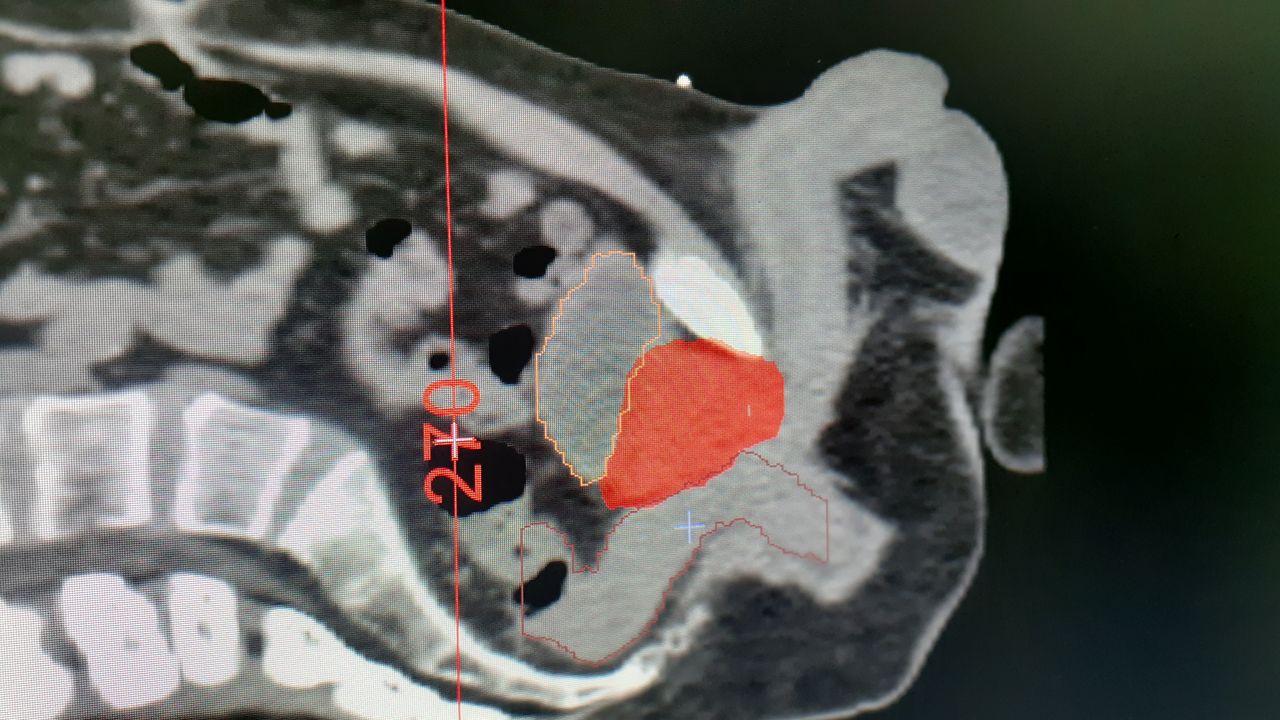

• Terapia de arco volumetrico modulado (VMAT)